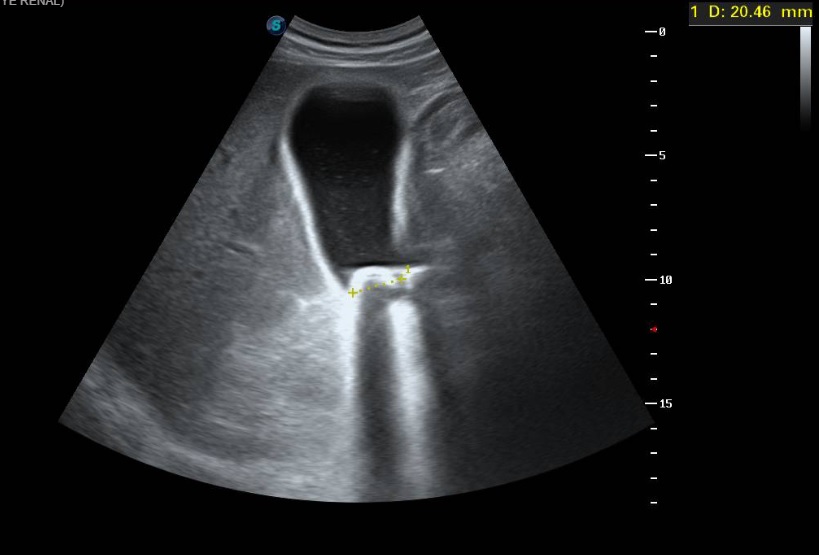

Ecografía clínica a pie de cama: Parénquima hepático y esplénico de ecoestructura preservada. Vesícula biliar marcadamente distendida con imagen hiperecogénica de 2 cm en porción declive compatible con litiasis. Dilatación de la vía biliar intrahepática difusa así como dilatación del colédoco.

La litiasis y la dilatación de la vesícula biliar encontrada en la ecografía clínica no justificaba todo el cuadro, por lo que solicitamos ecografía reglada al equipo de radiología. En ella informan marcada dilatación de la vía biliar intrahepática, con un colédoco de hasta 15 mm, y estructura mamelonada de aproximadamente 7 cm en cabeza pancreática. Se completa estudio con Tomografía Axial Computarizada que confirma masa en cabeza pancreática compatible con adenocarcinoma que condiciona dilatación de la vía biliar retrógrada.